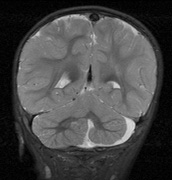

1. Superficial cortical sclerosis (parenchymal hamartoma) which distort the gyri. Microscopy shows large atypical fibrillary type astrocytes with few associated neurons and areas of calcification.133 The numerous abnormal glial processes and fibers make the tissue abnormally firm or “sclerotic” on palpation (Fig. 13).132

2. Subependymal nodules (SEN) are typically found along the lateral borders of the ventricles and parehncymal brain lesion (“cortical tubers”) (Figs. 14 and 15). Calcification in the first year of life is rare.132

On MRI imaging, the subependymal nodules and parenchymal brain lesions of infants (age ≤3 months) and adults show different signal characteristics. Infant CNS tubers are hyperintense on T1-weighted images and hypointense on T2-weighted images, which is the opposite of the pattern seen in adults.134 Malignant transformation of SEN occurs in about 10% to 15% of patients and the resultant subependymal giant cell astrocytoma accounts for 25% of premature deaths in TSC.135,136

Fig. 13. Tuberous Sclerosis Complex: “cortical sclerosis.” Numerous abnormal glial processes make the tissue abnormally firm or “sclerotic” on palpation.132

Fig. 14. Tuberous Sclerosis Complex: Sub-Ependymal nodules. These are typically found along the lateral borders of the ventricles.132

Fig. 15. Tuberous Sclerosis Complex. (a) Patient 1: Axial CT scans demonstrating typical calcification of subependymal nodules in a 13-year-old girl with a history of seizures. (b and c) Patient 2. (b) Axial T2-weighted images demonstrate calcified subependymal nodules (arrowheads) and cortical tubers typical of tuberous sclerosis. (c) Widespread cortical tubers are seen on a coronal FLAIR sequence as thickening of the cortex and high signal of the subcortical white matter.